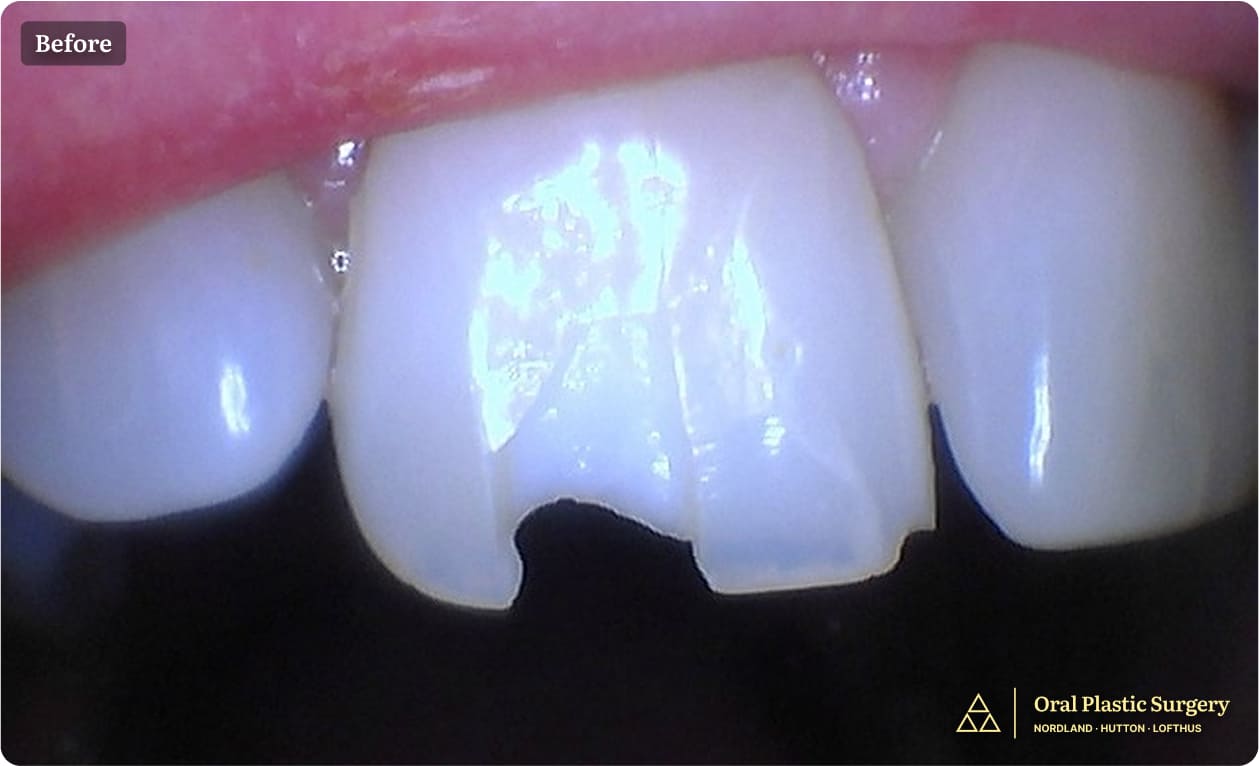

Excess gum display creating a "gummy smile" appearance. Note the short clinical crown length and disproportionate gum-to-tooth ratio